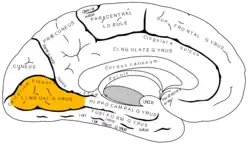

Medial surface of left cerebral hemisphere. (Lingual gyrus visible at left.) | |

The lingual gyrus of the occipital lobe lies between the calcarine sulcus and the posterior part of the collateral sulcus; behind, it reaches the occipital pole; in front, it is continued on to the tentorial surface of the temporal lobe, and joins the parahippocampal gyrus.[3]